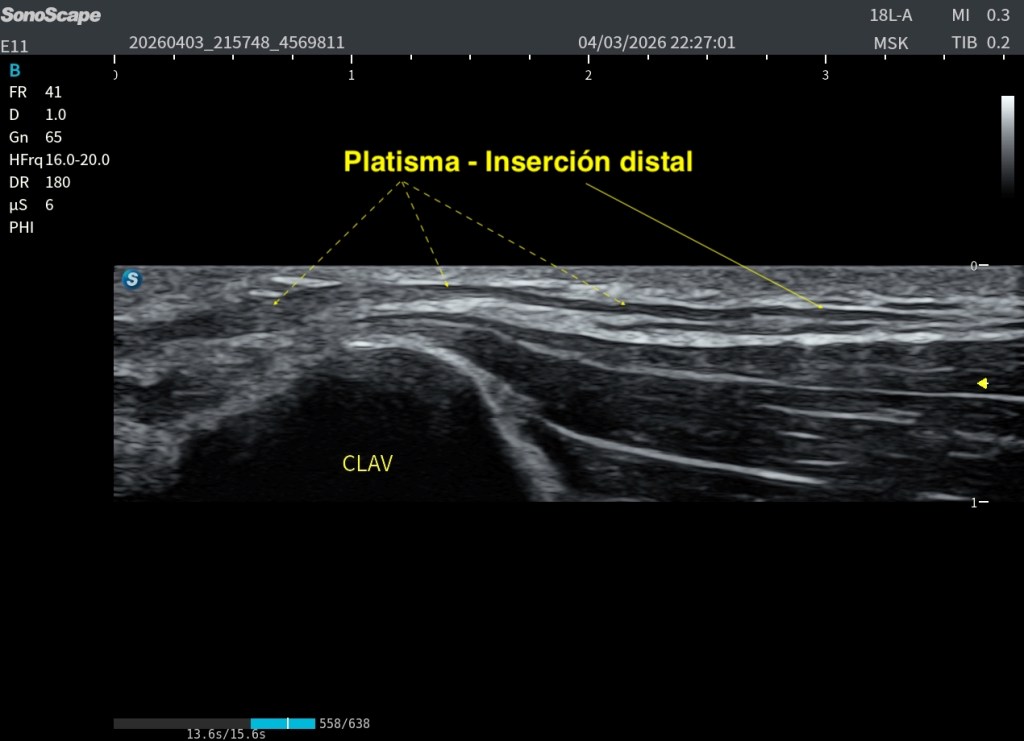

Su origen o porción caudal es difuso y superficial, localizado en el tejido subcutáneo infraclavicular y en la fascia superficial de la región clavicular, extendiéndose sobre el Pectoral mayor y el Deltoides. El estudio de Hwang K (2017) confirma que en la mayoría de los casos se inicia en la región torácica superior anterior a la clavícula, reforzando su naturaleza fascial y no ósea. Es un músculo apasionante.

El Platisma se presta especialmente bien a la evaluación mediante técnicas de campo extendido. Utilizando el modo panoramic view, es posible realizar un recorrido continuo del músculo y obtener una visión global de su extensión, algo muy útil dada su morfología plana y superficial.

La exploración puede realizarse en eje axial (corte corto respecto al cuello), desplazando la sonda de forma progresiva a lo largo del trayecto del músculo. Esto permite visualizar su continuidad lateral y entender mejor su disposición en el plano subcutáneo. También puede intentarse un estudio bilateral, tratando de integrar ambos lados en una única imagen panorámica.

A pesar de estas limitaciones, el platisma, por ser un músculo muy extenso, plano y superficial, se adapta bien a este tipo de exploración, y la panoramic view se convierte en una herramienta especialmente útil para comprender su anatomía global y su continuidad. Podemos medirlo tambien.